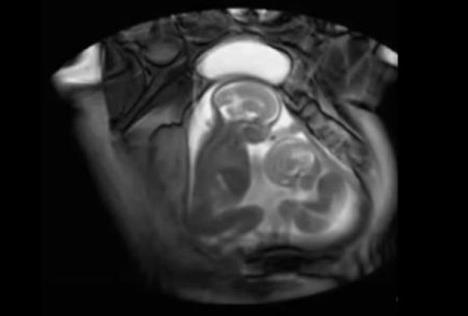

Ukoliko ste se pitali da li beba ima dovoljno mesta u maminom stomaku, zamislite kako je tek blizancima. Zahvaljujući snimku koji je nastao na Imperijal koledžu u Londonu, sada možemo da vidimo kako to zapravo izgleda kada dve bebe rastu u jednoj materici.

Naime, uz pomoću specijalnog skenera za magnetnu rezonancu koji se ne koristi pri uobičajenim pregledima u trudnoći, snimljene su bebe u materici, od kojih je jedna nešto veća, pa izgleda da drugi mališa mora na svaki način da se bori za svoje mesto.

Snimak inače beleži dvadesetu nedelju trudnoće.

Pogledajte ovaj neverovatni snimak: